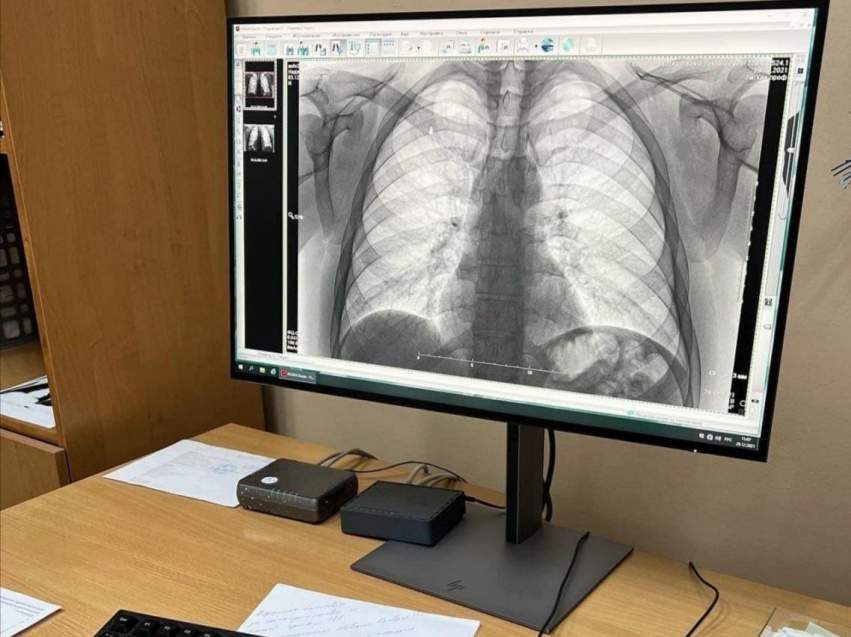

Необходимые тесты сделали все желающие бесплатно в День открытый дверей в краевом фтизиопульмонологическом центре. Пациентам сделали пробы манту, флюорографию и не только.

«Такие мероприятия мы делаем каждый год. В этот раз обследования прошли 120 человек, из них 20 детей. Помимо этого, мы проводим и другие акции. Например, наши волонтеры дарят надувные белые ромашки, как символ чистого дыхания, в центре города и рассказывают о профилактике заболеваний легких. Благодаря этому за прошлый год успешно пролечено около 400 человек», - рассказал руководитель центра Надежда Пикалова.